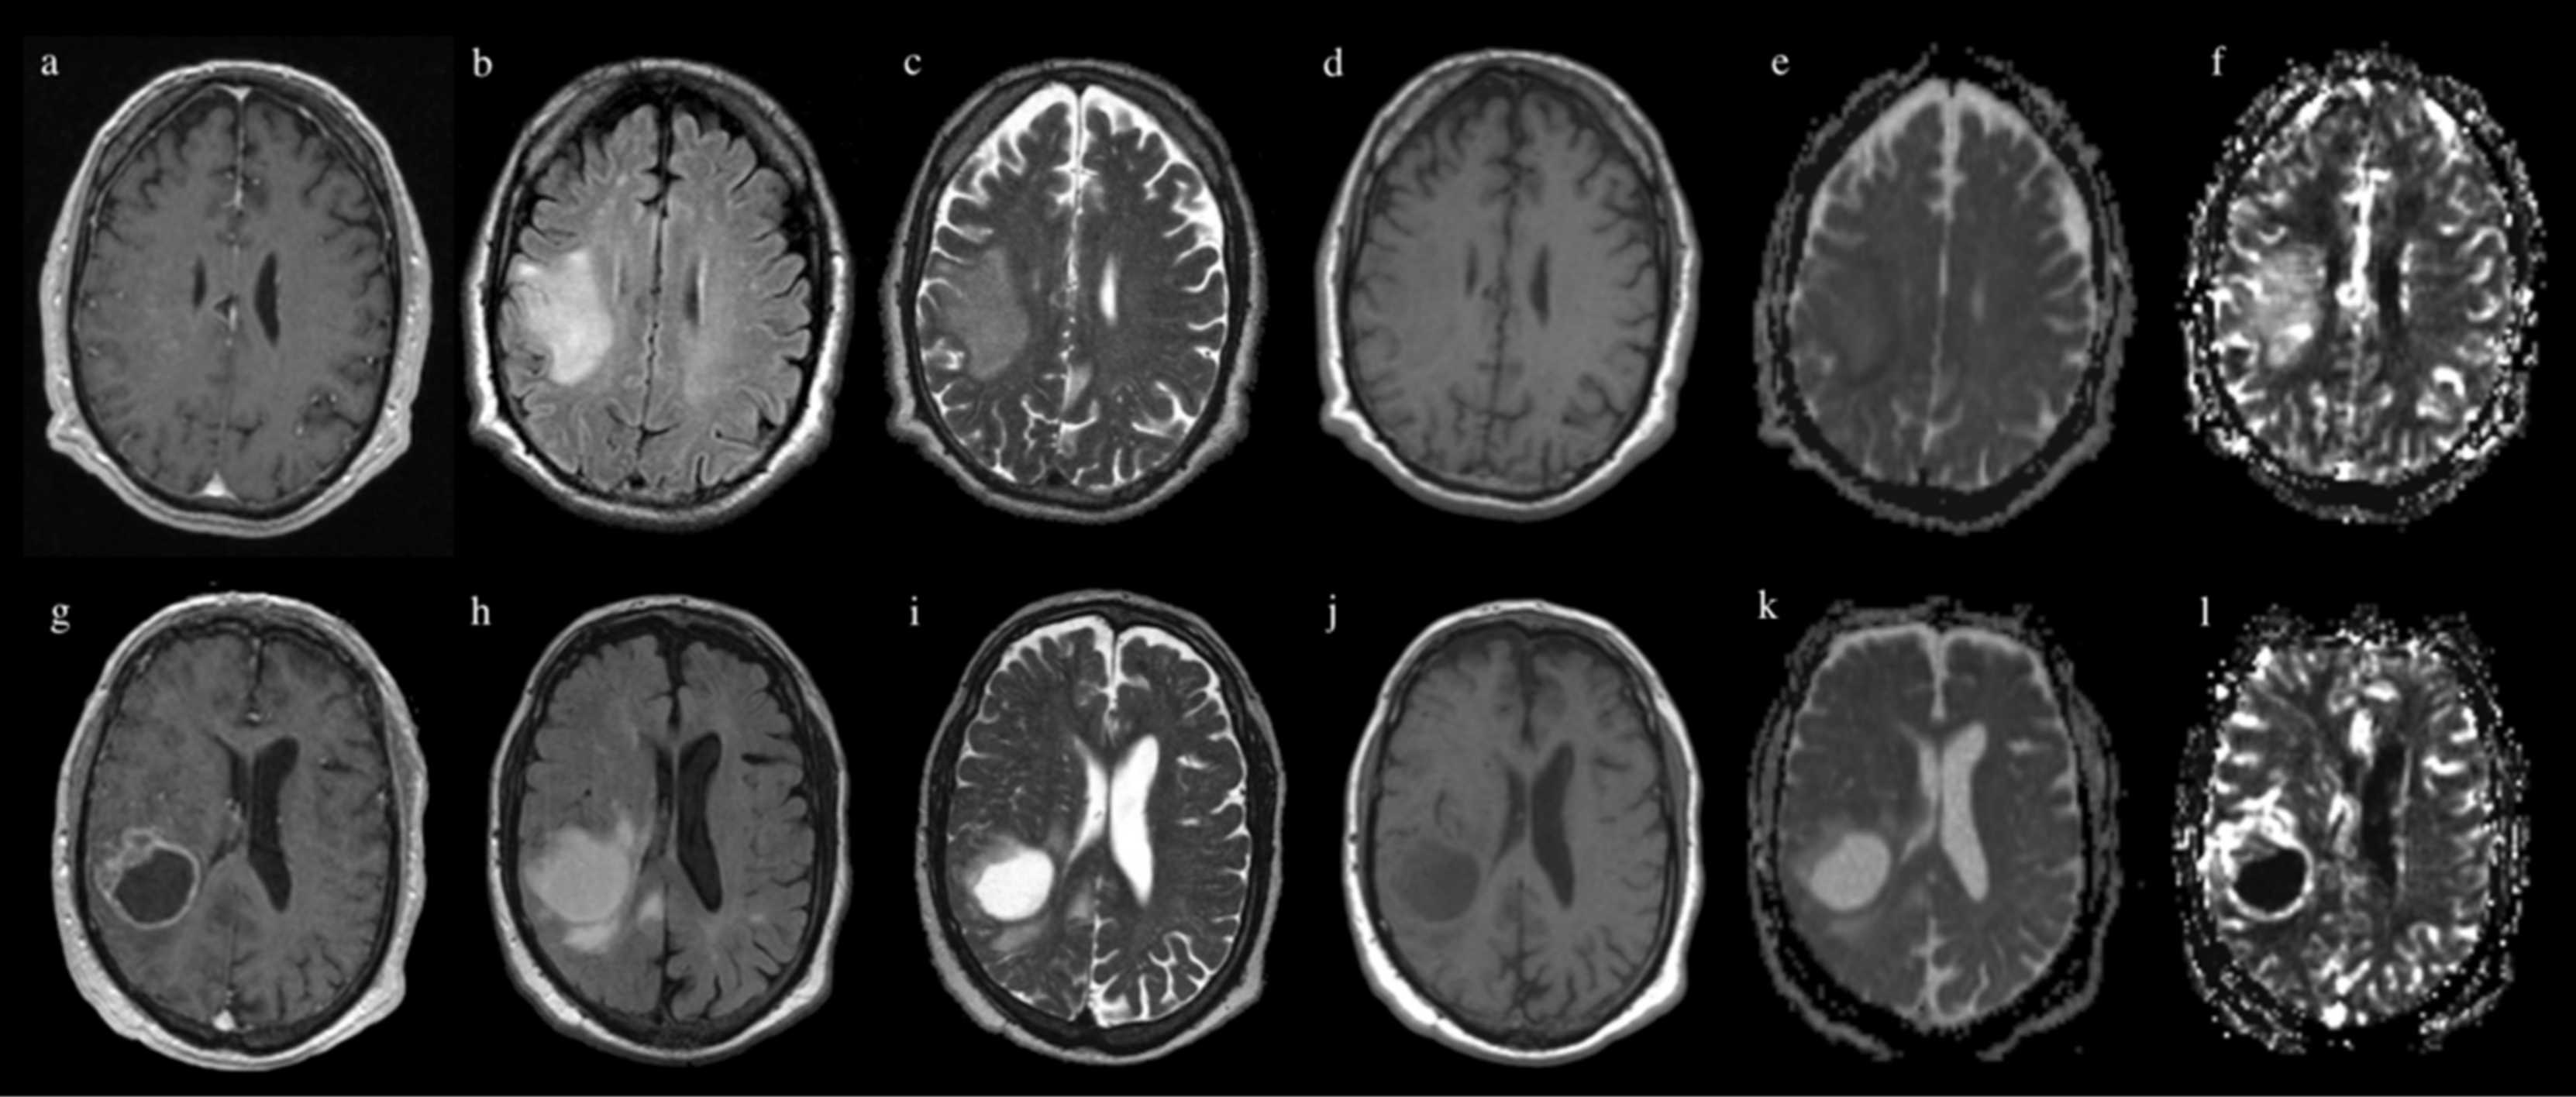

2. Materials and Methods

2.3. MR Image Acquisition

2.4. Image Processing

| Sequence | Test Acc | Test Loss | SN | SP | AUC |

|---|---|---|---|---|---|

| T1 | 0.77 ± 0.11 | 1.4± 09 | 0.36 ± 0.29 | 0.95 ± 0.07 | 0.71 ± 0.23 |

| T2 | 0.67 ± 0.12 | 2.41 ± 0.77 | 0.48 ± 0.16 | 0.75 ± 0.12 | 0.63 ± 0.07 |

| FLAIR | 0.77 ± 0.11 | 1.98 ± 1.06 | 0.28 ± 0.27 | 0.95 ± 0.03 | 0.74 ± 0.13 |

| MPRAGE | 0.66 ± 0.1 | 2.55 ± 0.93 | 0.43 ± 0.24 | 0.74 ± 0.17 | 0.62 ± 0.15 |

| rCBV | 0.83 ± 0.07 | 0.64 ± 0.23 | 0.76 ± 0.08 | 0.86 ± 0.08 | 0.86 ± 0.05 |

| ADC | 0.56 ± 0.11 | 2.53 ± 0.28 | 0.14 ± 0.07 | 0.73 ± 0.16 | 0.45 ± 0.04 |